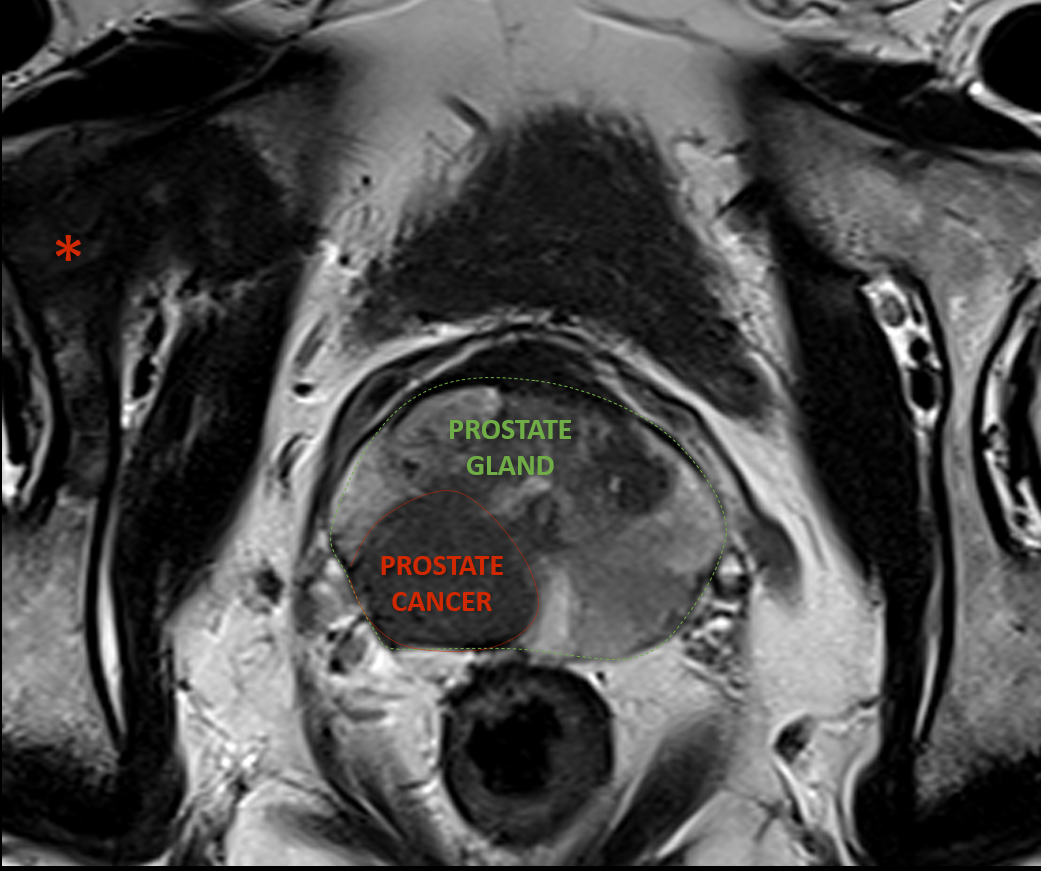

High-resolution MRI of the prostate shows two prostate cancers, one outlined in red.  MRI shows that the prostate cancer has grown beyond the capsule of the prostate gland.  In addition, there is a bone metastasis, shown by the asterisk.

When prostate cancer is suspected, Magnetic Resonance Imaging (MRI) can be used to evaluate the presence and local extent of the cancer or suggest alternative diagnoses.  By showing where the suspicious areas are in the prostate gland, MRI is used to help target ultrasound guided prostate biopsies, so the doctor doing the biopsy has the highest chance of sampling those parts of the prostate that are likely to have a tumour.

At TRG Imaging, we use state-of-the-art equipment, including high-field strength MRI, optimised multi-parametric pulse sequences (mpMRI), and (at some sites) artificial intelligence image reconstruction software to generate very high-resolution images of the prostate gland.  This allows our specialist radiologists to identify and classify tumours, evaluate for extension beyond the prostate gland, and look for lymph node involvement and seminal vesicle invasion.  Our radiologists use structured reports incorporating the ACR / ESUR PI-RADS prostate classification system to precisely communicate the results to urologists and oncologists so that each individual patient is provided with the most appropriate treatment options.  Using the latest equipment and structured reporting systems also allows us to reduce the number of unnecessary biopsies by identifying very low-risk prostate nodules.